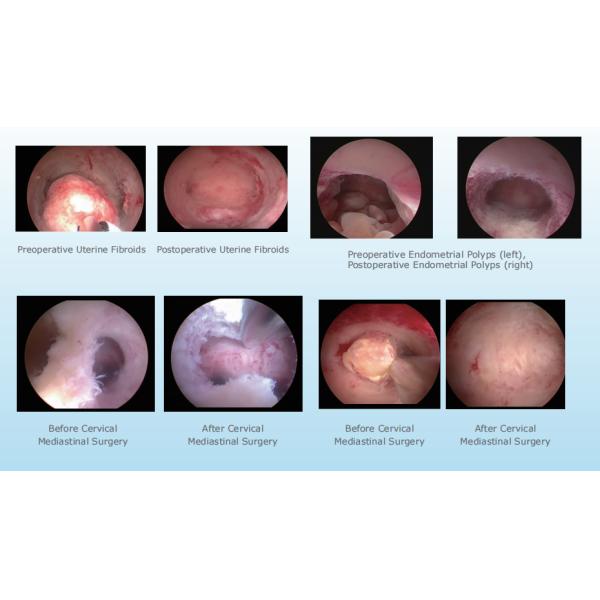

Indications : Endometrial polyps, submucosal fibroids, cornual pregnancy, retained products of conception, intrauterine adhesions

| Indications: | Endometrial polyps, submucosal fibroids, cornual pregnancy, retained products of conception, intrauterine adhesions |

The Better Health BH-300 surgical power system is designed for a multitude of product application occasions and scenarios. This manual morcellation cutter surgical power system intrauterine solution is perfect for gynecological surgeries, such as hysterectomies, myomectomies, and cystectomies. The easy operation of this surgical power system allows for efficient tissue removal, while the central direct suction channel ensures a clean surgical field. The automatic motor identification feature saves time and increases efficiency, allowing for a seamless surgical procedure.

The Better Health BH-300 surgical power system comes with an intrauterine solution that includes saline solution for uterine expansion. This feature makes it ideal for surgeries that require uterine manipulation and expansion, such as endometrial ablation and hysteroscopy. The roller pump for tissue removal ensures that the surgical field is clean and free of debris, while the central direct suction channel provides additional suction for a clear view of the surgical site.